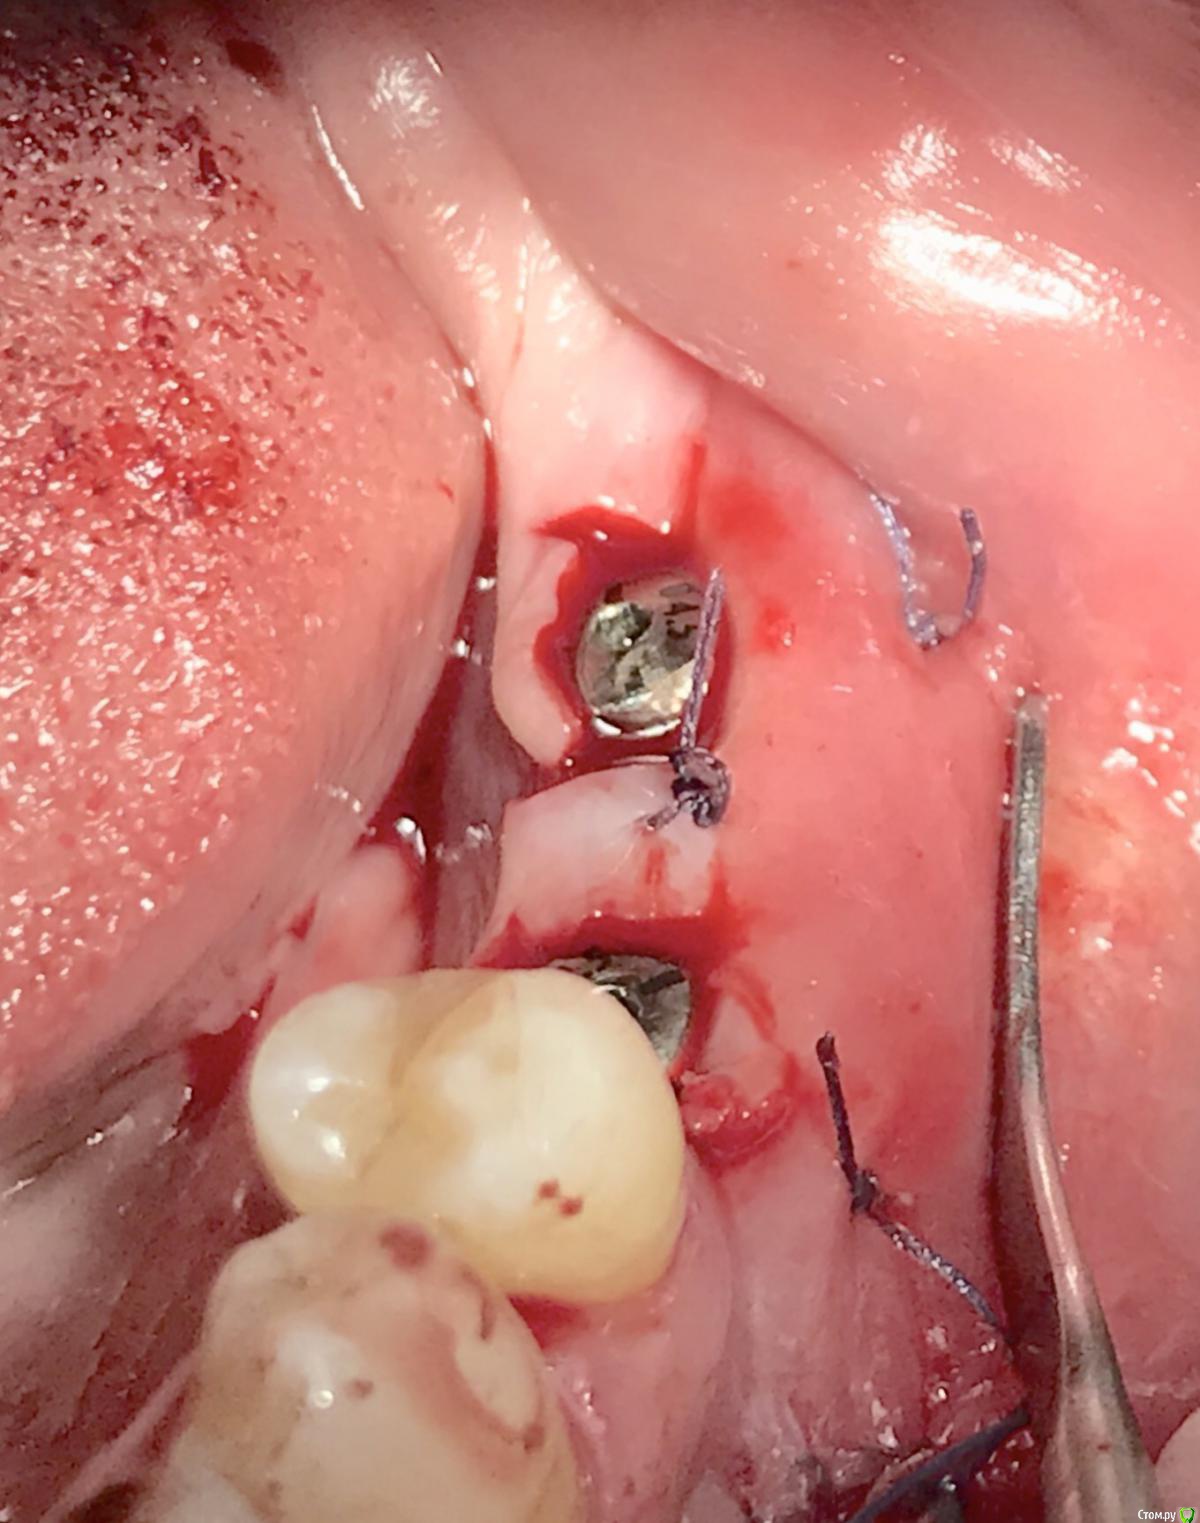

колесников Опубликовано 16 декабря, 2018 Автор Поделиться Опубликовано 16 декабря, 2018 (изменено) Поставлена задача:возместить дефект зубного ряда. Бюджет ограничен. Как видно по кт,для имплантации нет сложностей. Импланты Астра 4.0,поставлены с заглублением в оптимальной позиции. Дефицит прикреплённой слизистой вестибулярно у шеек имплантов возмещён роллом с гребня. Можно было этим ограничится. Однако при протезировании дефицит объема тканей будет очевиден. Роллы фиксированы к подвижной и тонкой слизистой,результат сомнительный,тк нет стабильности. Щечный тяж и скат гребня неминуемо приведут к рецесси слизистой у шеек имплантов. Можно было восстановить объём гребня при помощи нкр,затем лоскут с неба ( 1 год лечения). Или хотябы подсадить сст пожирнее.а потом асл (6мес),на первое время хватило бы. Но . Бюджет ограничен. Сроки тоже. Слово «костная пластика» вызывает панику. Новая задача: минимизировать вмешательства,убрать тяжи,создать объём,небо не трогаем. Проводим тоннельный графтинг. Получаем объём,поднимаем ткани и тяжи не тянут. Роллы получают покой ,стабильность и созревают в кратчайшие сроки. Графт поднадкостнично. Графт стабилен. Графт пропитался кровью,графт созревает. Результат быстрый. Дискомфорта 0. Затраты минимальные. Срок жизни такой пластики ни чем отличается от любой другой,в конечном итоге тает все. Если не стимулировать. Изменено 16 декабря, 2018 пользователем колесников 1 Ссылка на комментарий

колесников Опубликовано 19 декабря, 2018 Автор Поделиться Опубликовано 19 декабря, 2018 Чтобы ролл зафиксировать . Ссылка на комментарий